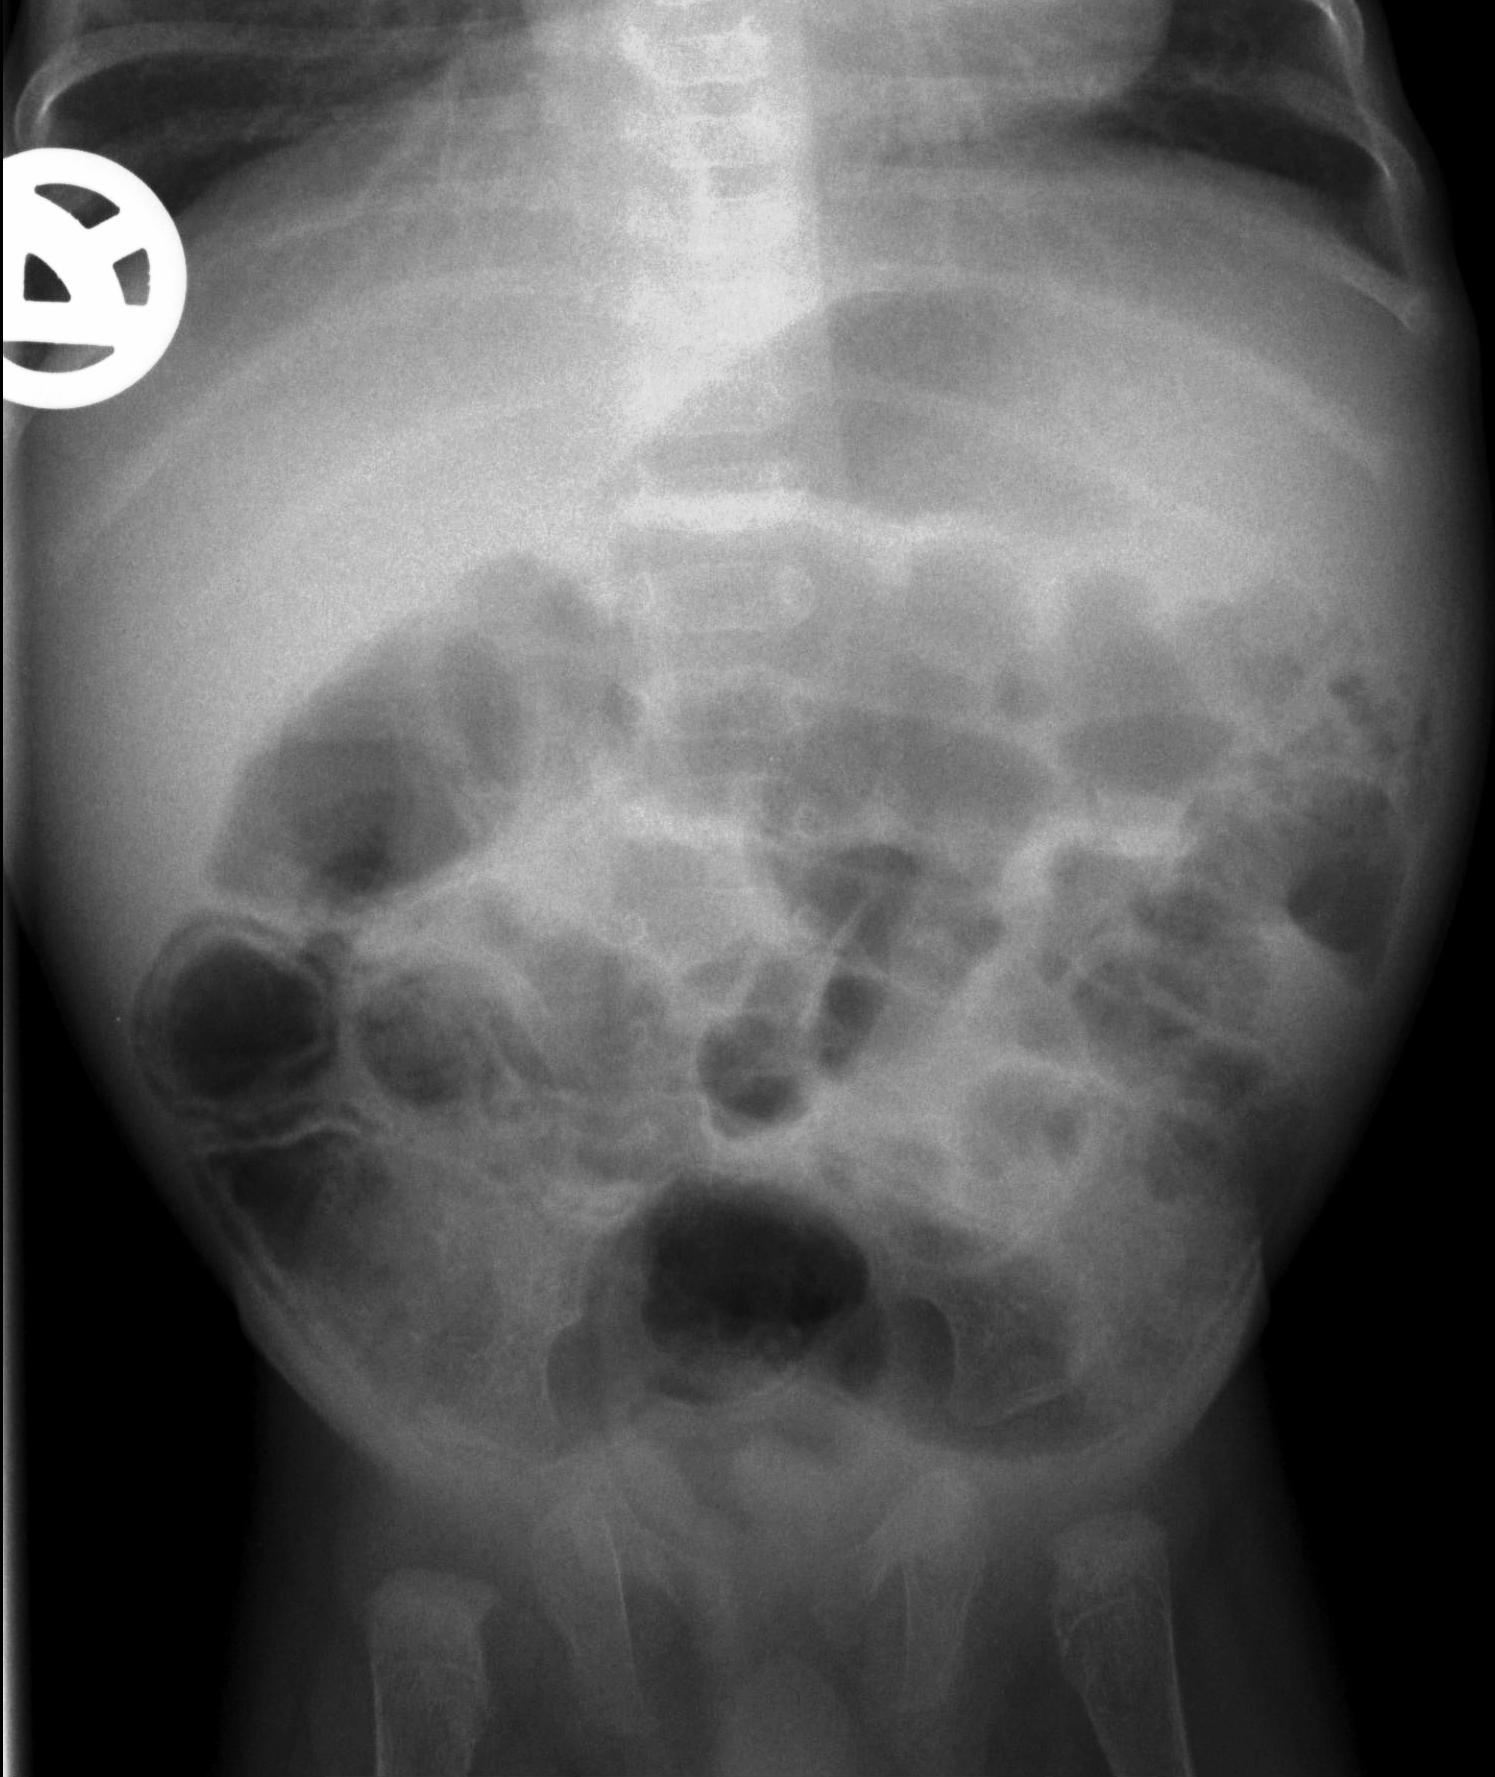

Hirschsprung-disease. In this disease the ganglions of the distal colon are missing. The lack of innervation of the colonic smooth muscle results in spastic functional obstruction. The symptoms can appear right after birth with the lack of meconium defecation and signs of obstruction. On plain abdominal X-ray the proximal intestines are distended with or without air-fluid levels, the distal loops are gas free. With contrast enema the distal, irregular, spastic, non-innervated segments and the proximal prestenotic dilatation of the colon can be visualized.

21. The distal segment of the colon is narrow, irregular (aganglionar segment). Transitional zone (arrow) and compensatory prestenotic dilatation. Hirschsprung-disease.